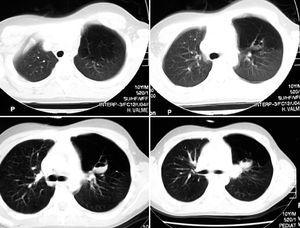

Figura 2.TC pulmonar en la cual se evidencia en los cortes pulmonares altos la hiperclaridad pulmonar con disminución de la vascularización, que afecta al lóbulo superior izquierdo. A nivel hiliar izquierdo y, justo encima de la salida del bronquio del lóbulo superior izquierdo, se aprecia una imagen seudonodular de 2 cm de diámetro. Mediante contraste se evidencia la doble luz de contenido de + 5 u/H en los dos tercios inferiores.

La TC torácica permite la visualización del broncocele, de la hiperinsuflación segmentaria y de la hipovascularización. La combinación de todos ellos puede considerarse diagnóstica de atresia bronquial congénita. La TC es hoy día el procedimiento diagnóstico de elección5,9, puede demostrar la ausencia de comunicación entre el broncocele y el hilio y es más sensible que la radiografía simple en la demostración de la hiperinsuflación pulmonar4. La TC con contraste permite excluir anomalías vasculares sin la necesidad de realizar una angiografía pulmonar. La TC en espiración puede demostrar el atrapamiento aéreo10.